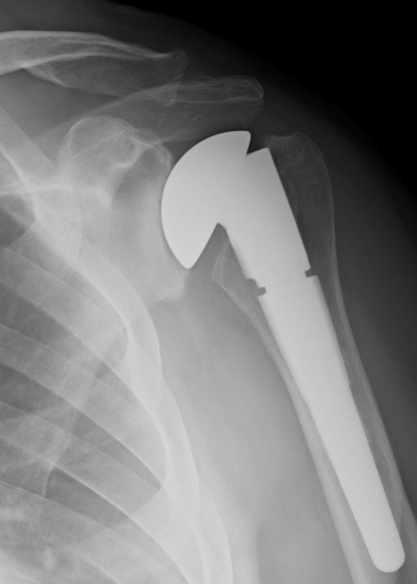

Hemiarthroplasty

Hemiarthroplasty (young patient or insufficient glenoid bone stock)

- systematic review of aTSA v hemiarthroplasty for OA with intact cuff

- 8% better functional outcomes with aTSA

- double revision rate and complications with HA

Painful hemiarthroplasty revised to aTSA